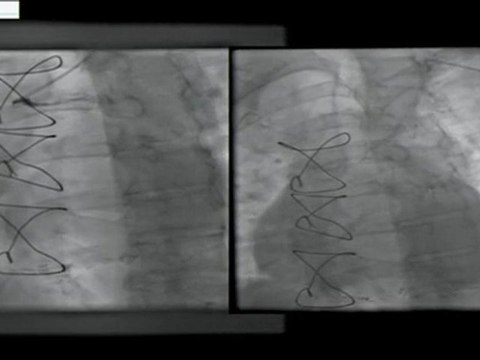

bilateral, internal, mammary, artery, graft, angiogram, radial, approach, incathlab